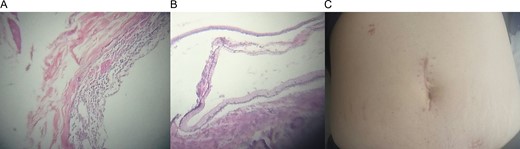

The right colon with the mass was completely resected through a small midline incision without complications. The external surface of the mass was pinkish-gray color and the cystic wall was even in thickness ~0.4 cm (Fig. 1C) and contained clear mucous fluid. Pathology reported intestinal duplication cyst, microscopically, the cystic wall partially consisted of normal mucosa, submucosa, smooth muscle and serosa (Fig. 2A and B). No epithelial dysplasia or malignancy was evident.

(A) Microscopic view of the cystic wall. (B) Normal colonic wall adjacent to the cystic wall. (C) Midline incision after recovery.

On follow up controls patient was completely asymptomatic, without any pain or complications (Fig. 2C).